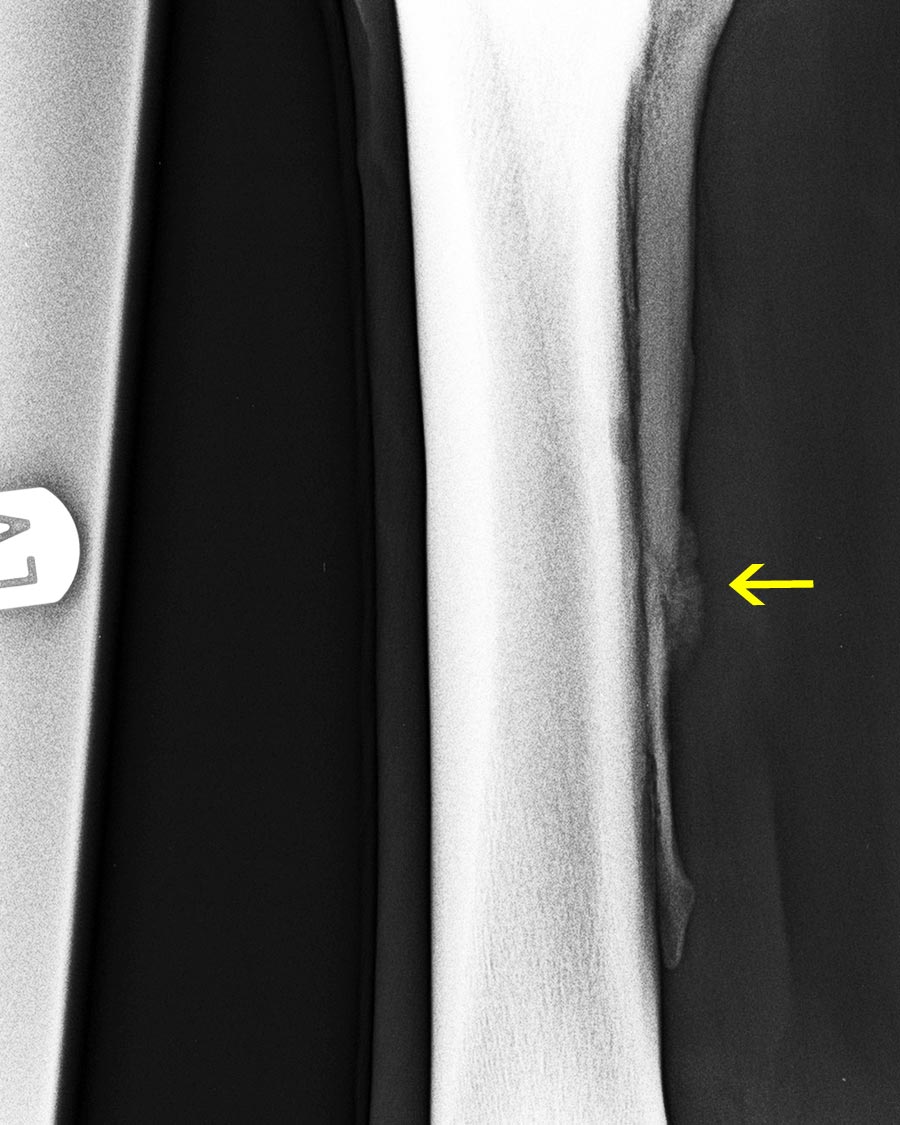

großes Überbein innen am Röhrbein (gelber Pfeil)